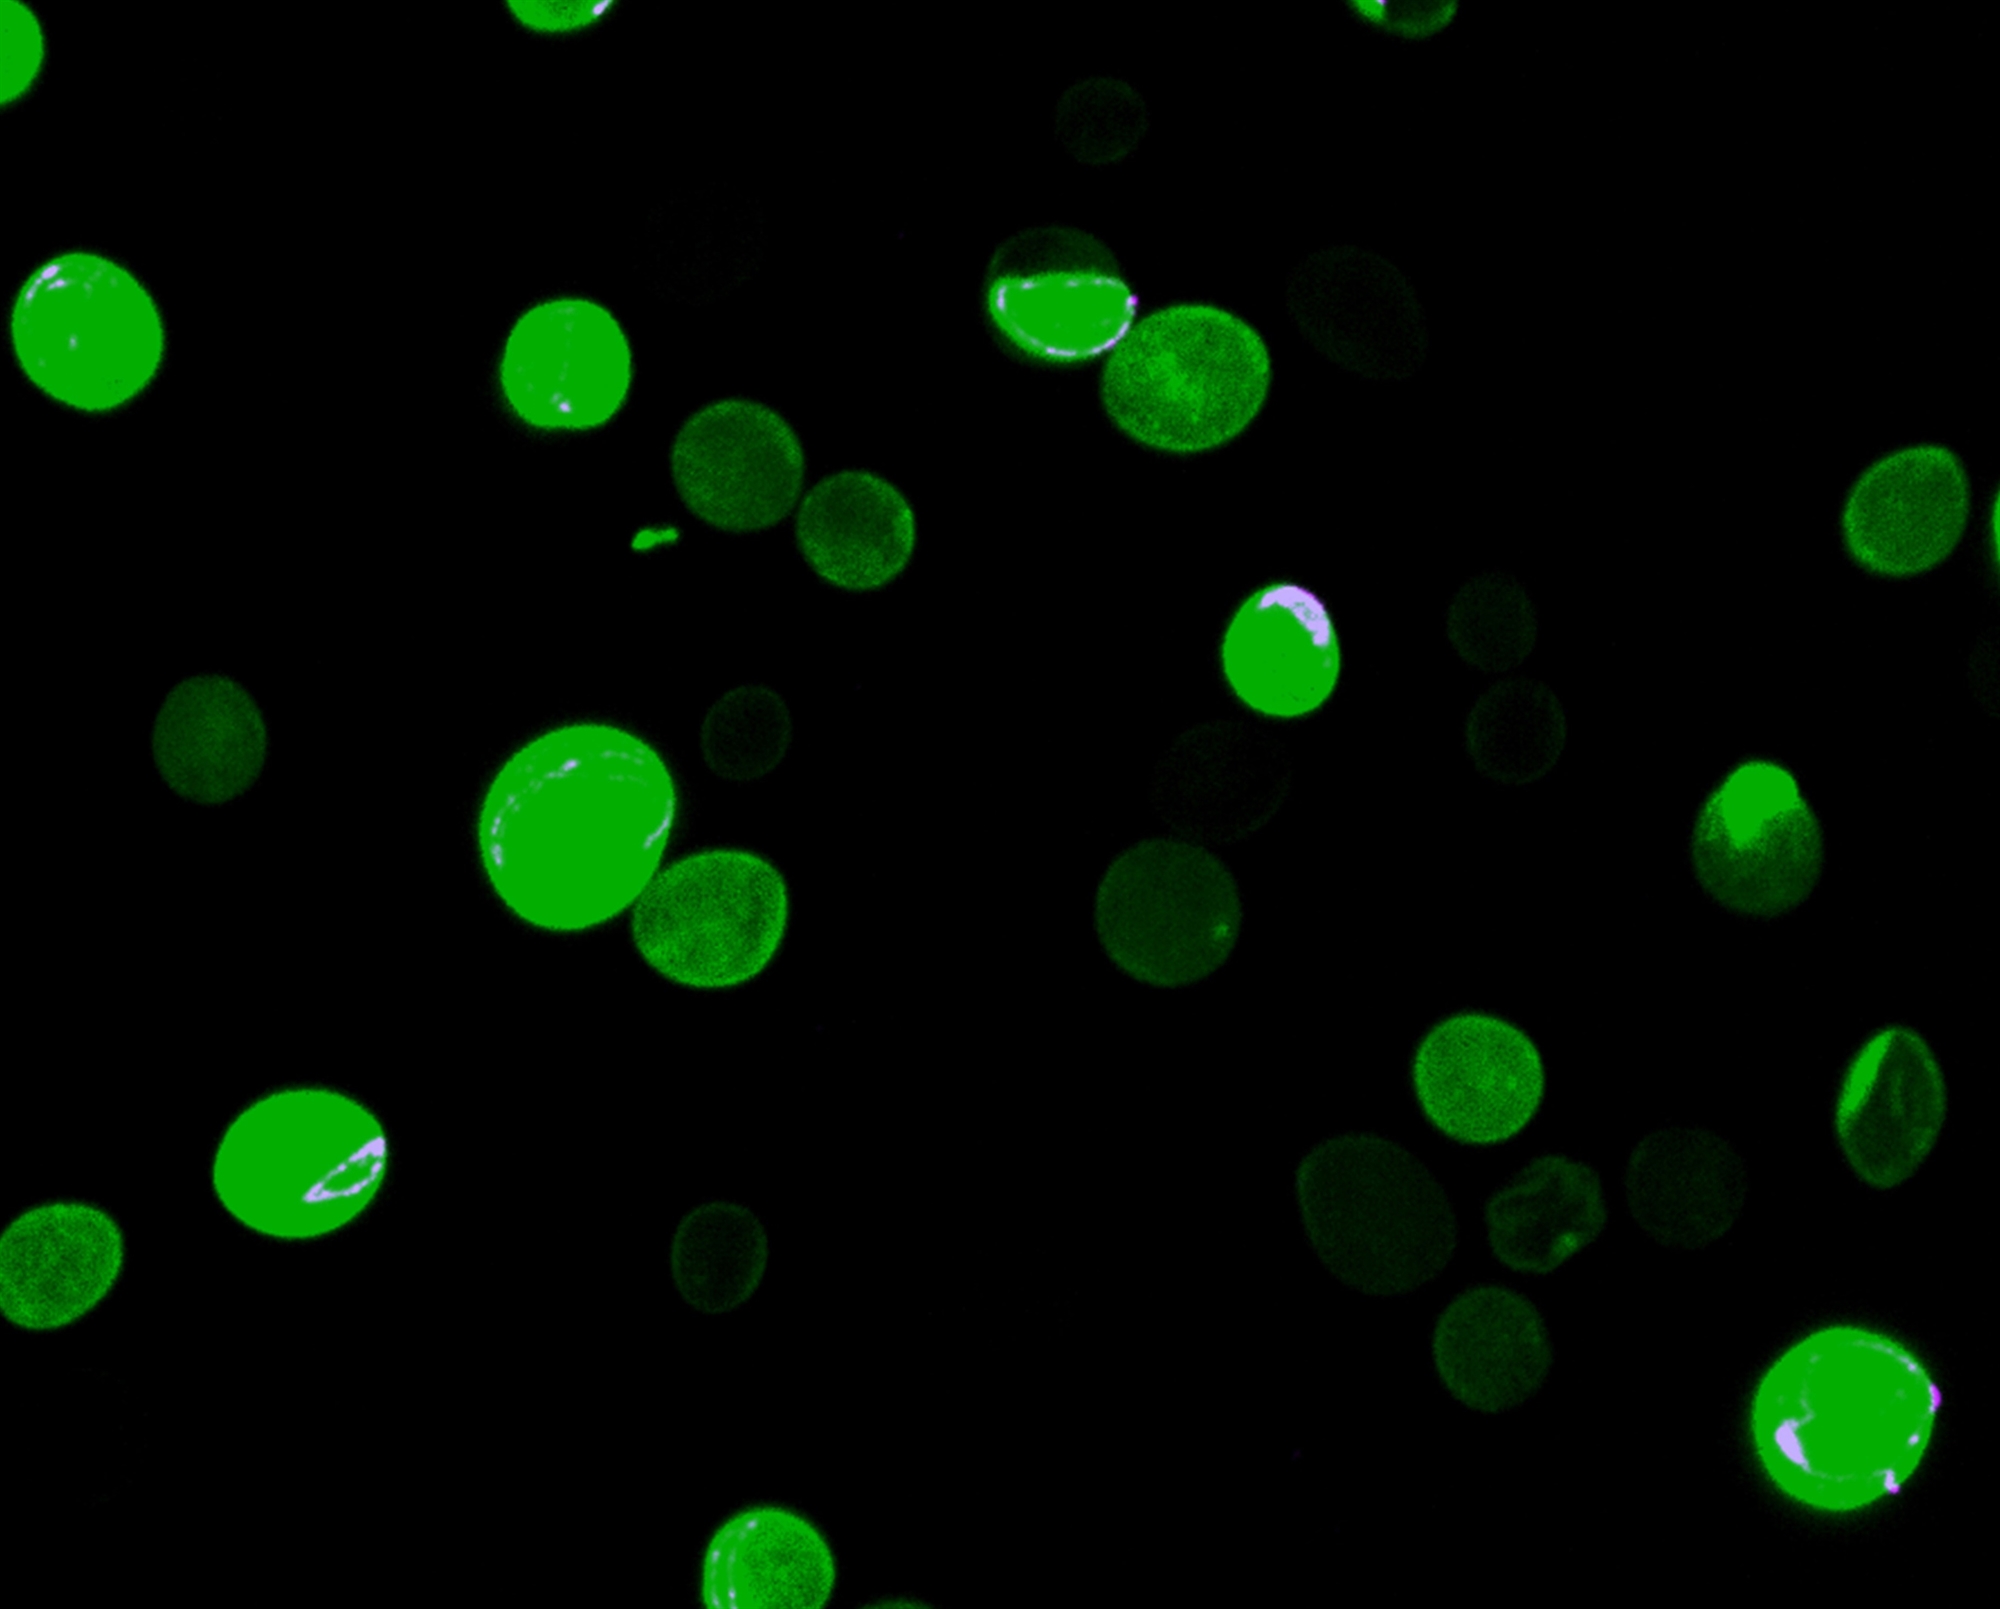

Η ομάδα του διαπίστωσε ότι οι ασθενείς με μουκορμυκητίαση έχουν σημαντικά χαμηλότερα επίπεδα αλβουμίνης σε σύγκριση με ασθενείς που πάσχουν από άλλες διηθητικές μυκητιάσεις, ενώ η σοβαρή υποαλβουμιναιμία αποτελεί τον ισχυρότερο προγνωστικό δείκτη κακής έκβασης. «Η αλβουμίνη δρα εντυπωσιακά: αναστέλλει επιλεκτικά την ανάπτυξη των μυκήτων Mucorales», εξηγεί ο Γιώργος Χαμηλός. «Τα δεσμευμένα στο μόριό της ελεύθερα λιπαρά οξέα παίζουν κρίσιμο ρόλο στην άμυνα του οργανισμού. Μπορούν να εισέλθουν στον μύκητα και να τον εμποδίσουν να ενεργοποιήσει γονίδια απαραίτητα για την ανάπτυξή του. Με άλλα λόγια, καθιστούν το παθογόνο ανίκανο να προκαλέσει νόσο». Η χορήγησή της γίνεται με ενδοφλέβια έγχυση και, «σε αντίθεση με αντιμυκητιασικά φάρμακα που ενδέχεται να προκαλέσουν παρενέργειες, δεν έχει τοξικότητα, δεν είναι σε καμιά περίπτωση επιβλαβής για τους ασθενείς». Οι Ελληνες επιστήμονες, σε συνεργασία με κορυφαίο αιματολογικό κέντρο της Ευρώπης, ετοιμάζουν τη δεύτερη φάση της μελέτης, η οποία θα συμπεριλάβει αιματολογικούς ασθενείς με πολύ χαμηλά επίπεδα αλβουμίνης. Σε αυτούς θα χορηγηθεί η πρωτεΐνη και θα αξιολογηθεί η ανοσολογική τους απόκριση.